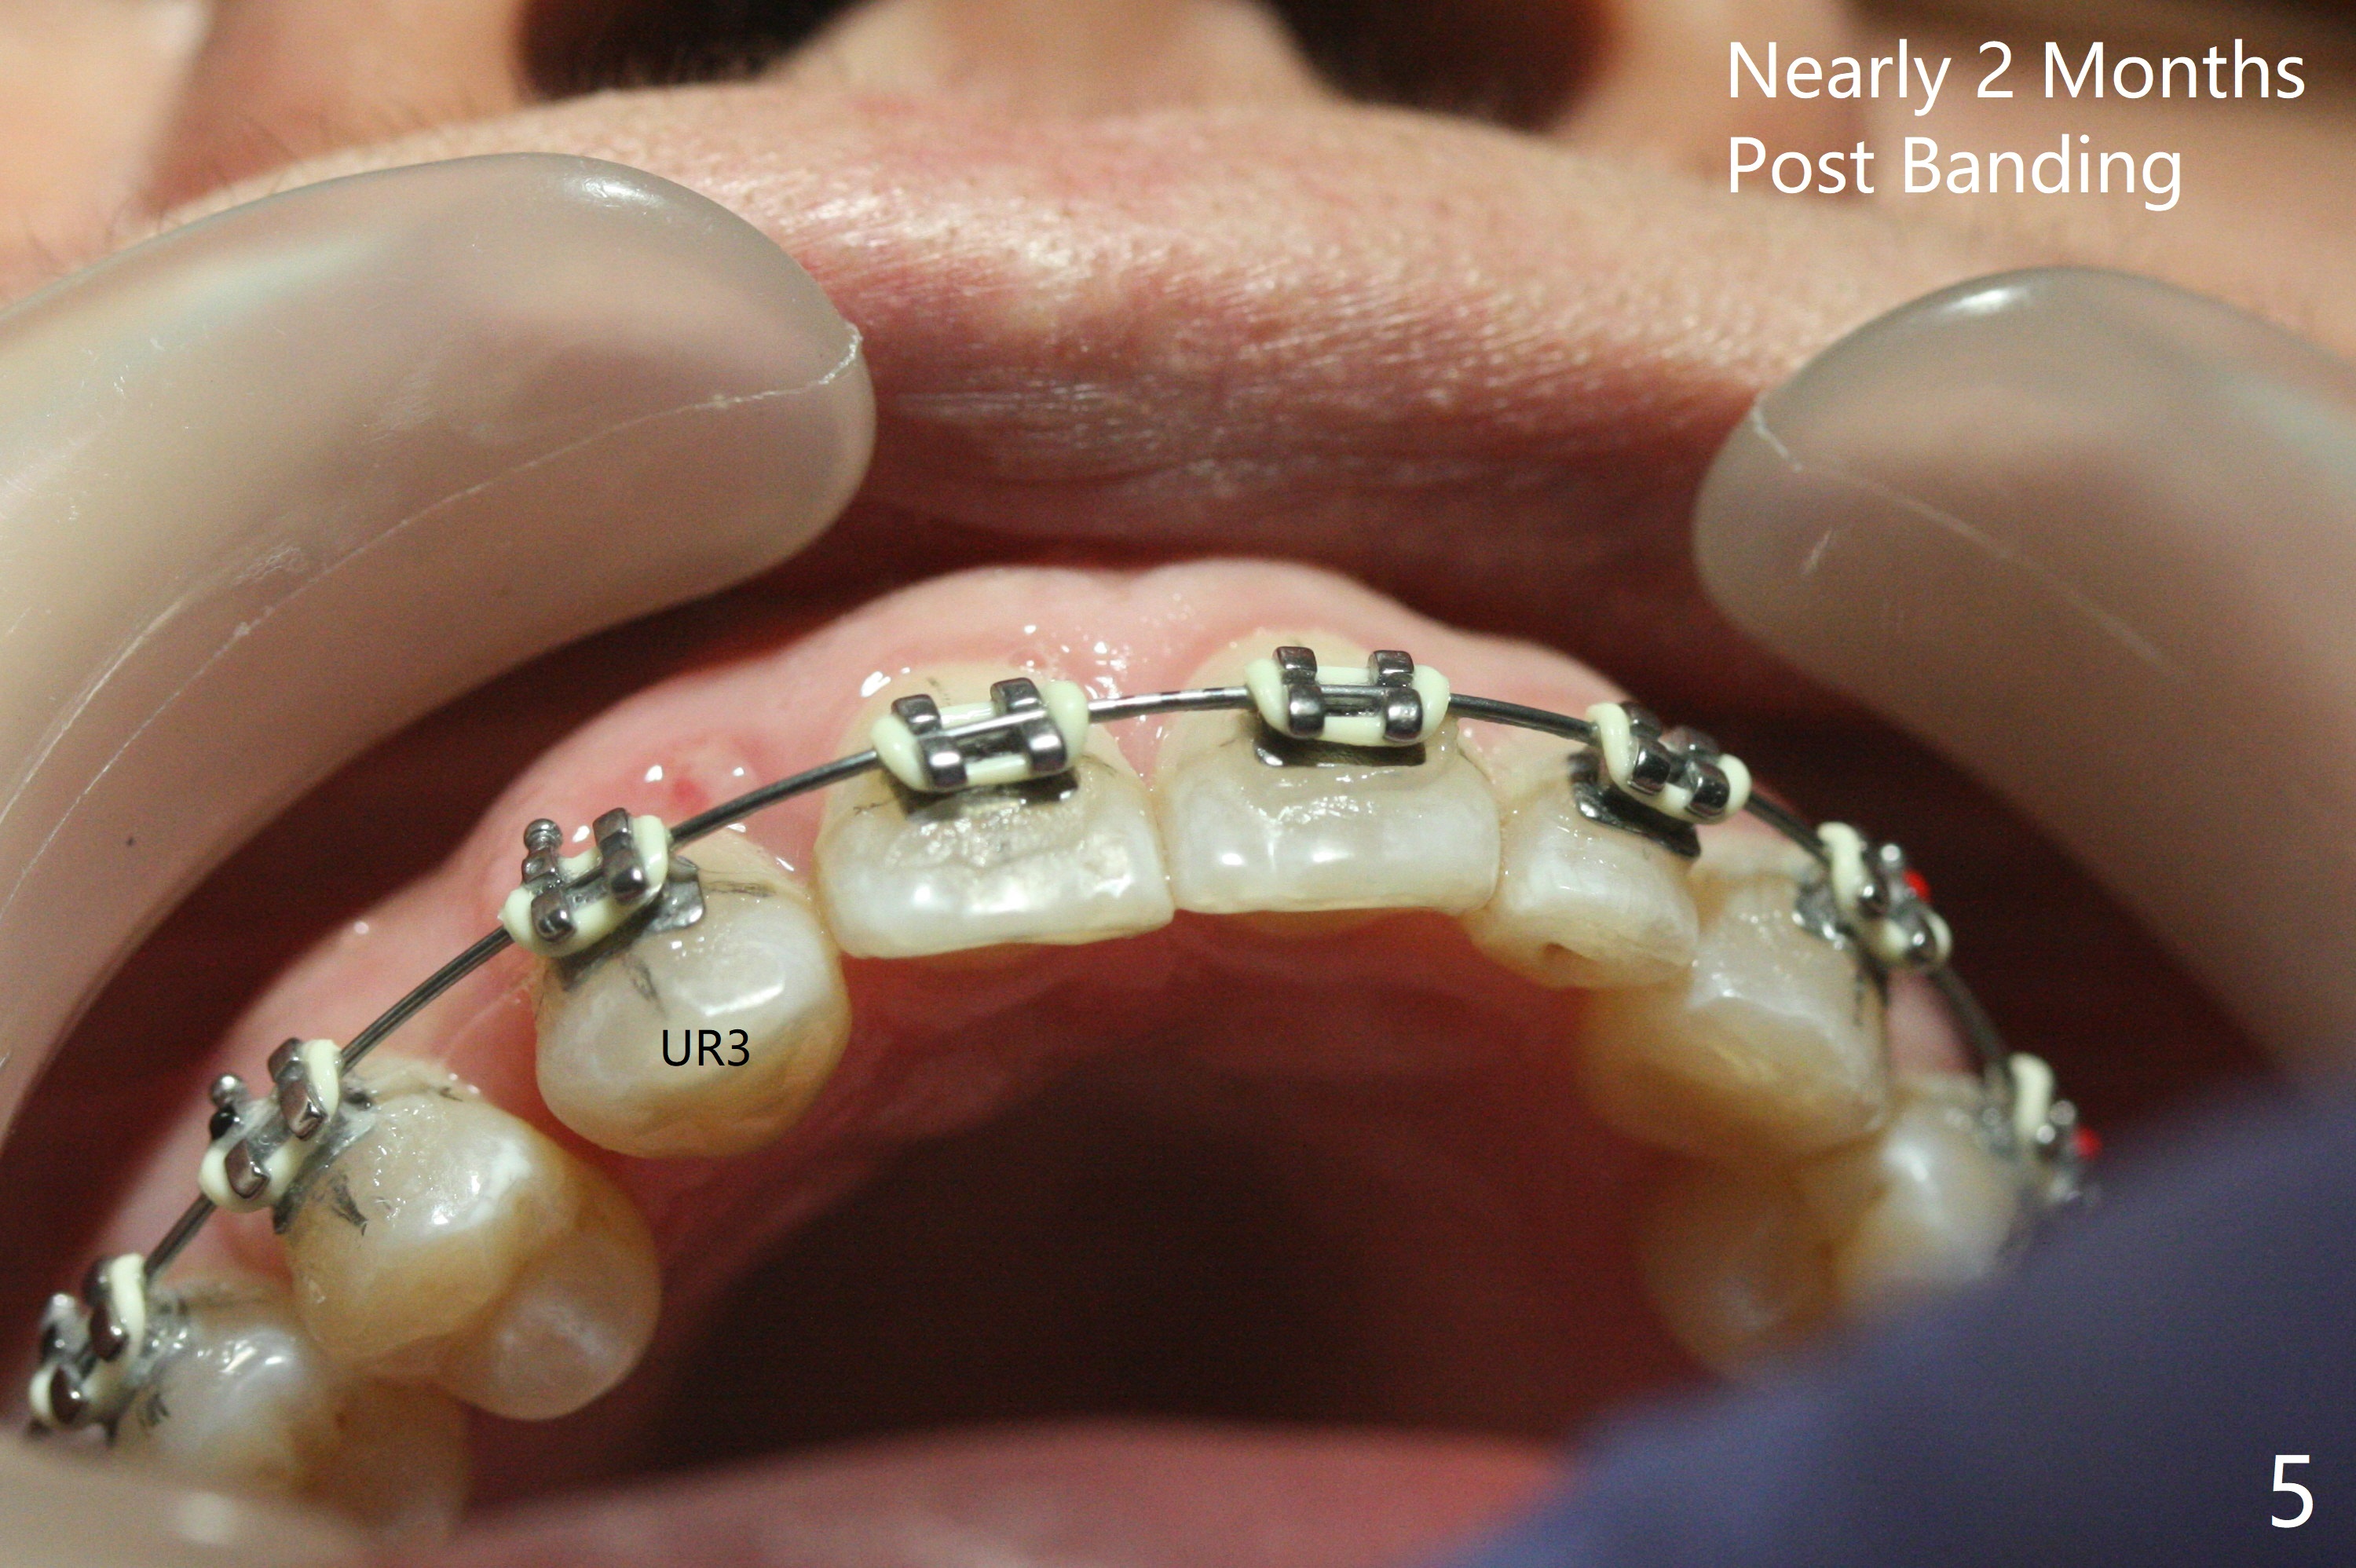

The 54-year-old woman returns for ortho-dontic treatment 1.5 months post extra-ction of UR2 (Fig.1,2). Brackets, bands and 14 niti wire are placed in the upper arch, whereas insufficient spaces are created for placement of the lower arch molar bands. Since there is no horizontal space issue, the cross bite canine is able to be corrected immediately when the vertical clearance is obtained (Fig.3,4). In fact composite is added to the 1st molars in a few days, since that in one of the 2nd molars dislodges. UR3 cross bite is nearly corrected < 2 months post banding (Fig.5), while brackets are placed in the lower arch (Fig.6 (coronavirus)). It appears that the lower arch will be too large when it is expanded for the upper one.